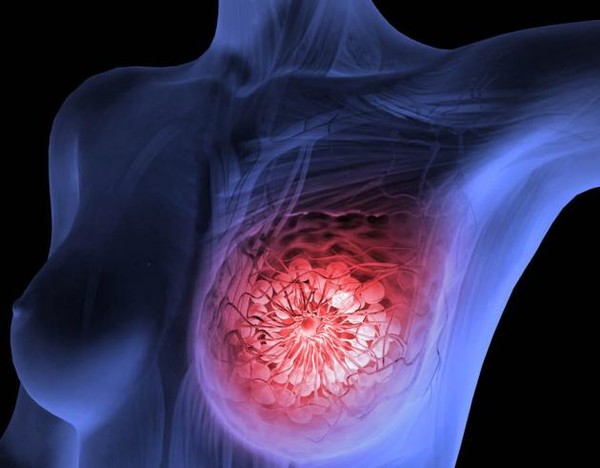

전 세계 여성 3명 중 1명이 암에 걸린다고 알려진 유방암에 좋은 음식과 유방암에 나쁜 음식에 대해서 살펴보도록 하겠습니다. 유방암은 갑상선암에 이어 여성에게 두 번째로 흔한 암이며, 중년 여성의 암 사망률 1위입니다.

유방암은 유방에서 발생하는 모든 악성 종양의 그룹이라고 합니다. 유방암은 유방의 비정상적인 조직이 계속 자라거나 다른 장기로 퍼지는 위험한 질병이라고 합니다. 가장 두드러진 원인은 DNA 손상 및 유전자 돌연변이와 같은 유전적 조건입니다.